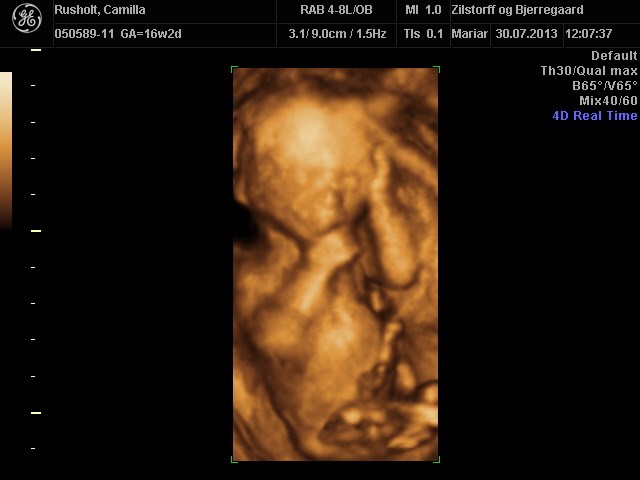

CroQuis skriver:

Årrrrrrh hvor er han fin

Hvad koster det egentlig at få 3D og alle de billeder/film med?

Vi gav 700 kr

Vi køber så også 3d/4d scanning hos dem i uge 28, og så får man så rabat på den. Den koster 1400, men vi skal kun give 1100 (fordi vi har fået kønsscanning der også), og så får vi 300 tilbage af danmark, så alt i alt 1700 kr for 3d/4d scanning samt kønsscanning med 3d